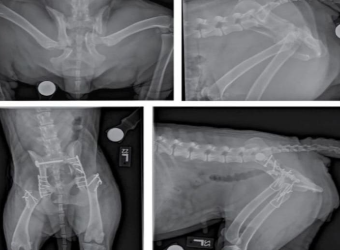

Phẫu thuật xương khớp cho thú cưng tại Sing Pet Biên Hòa, Đồng Nai. Bác sĩ giỏi, trang thiết bị hiện đại, chăm sóc hậu phẫu tận tâm, giúp thú cưng hồi phục nhanh và an toàn.